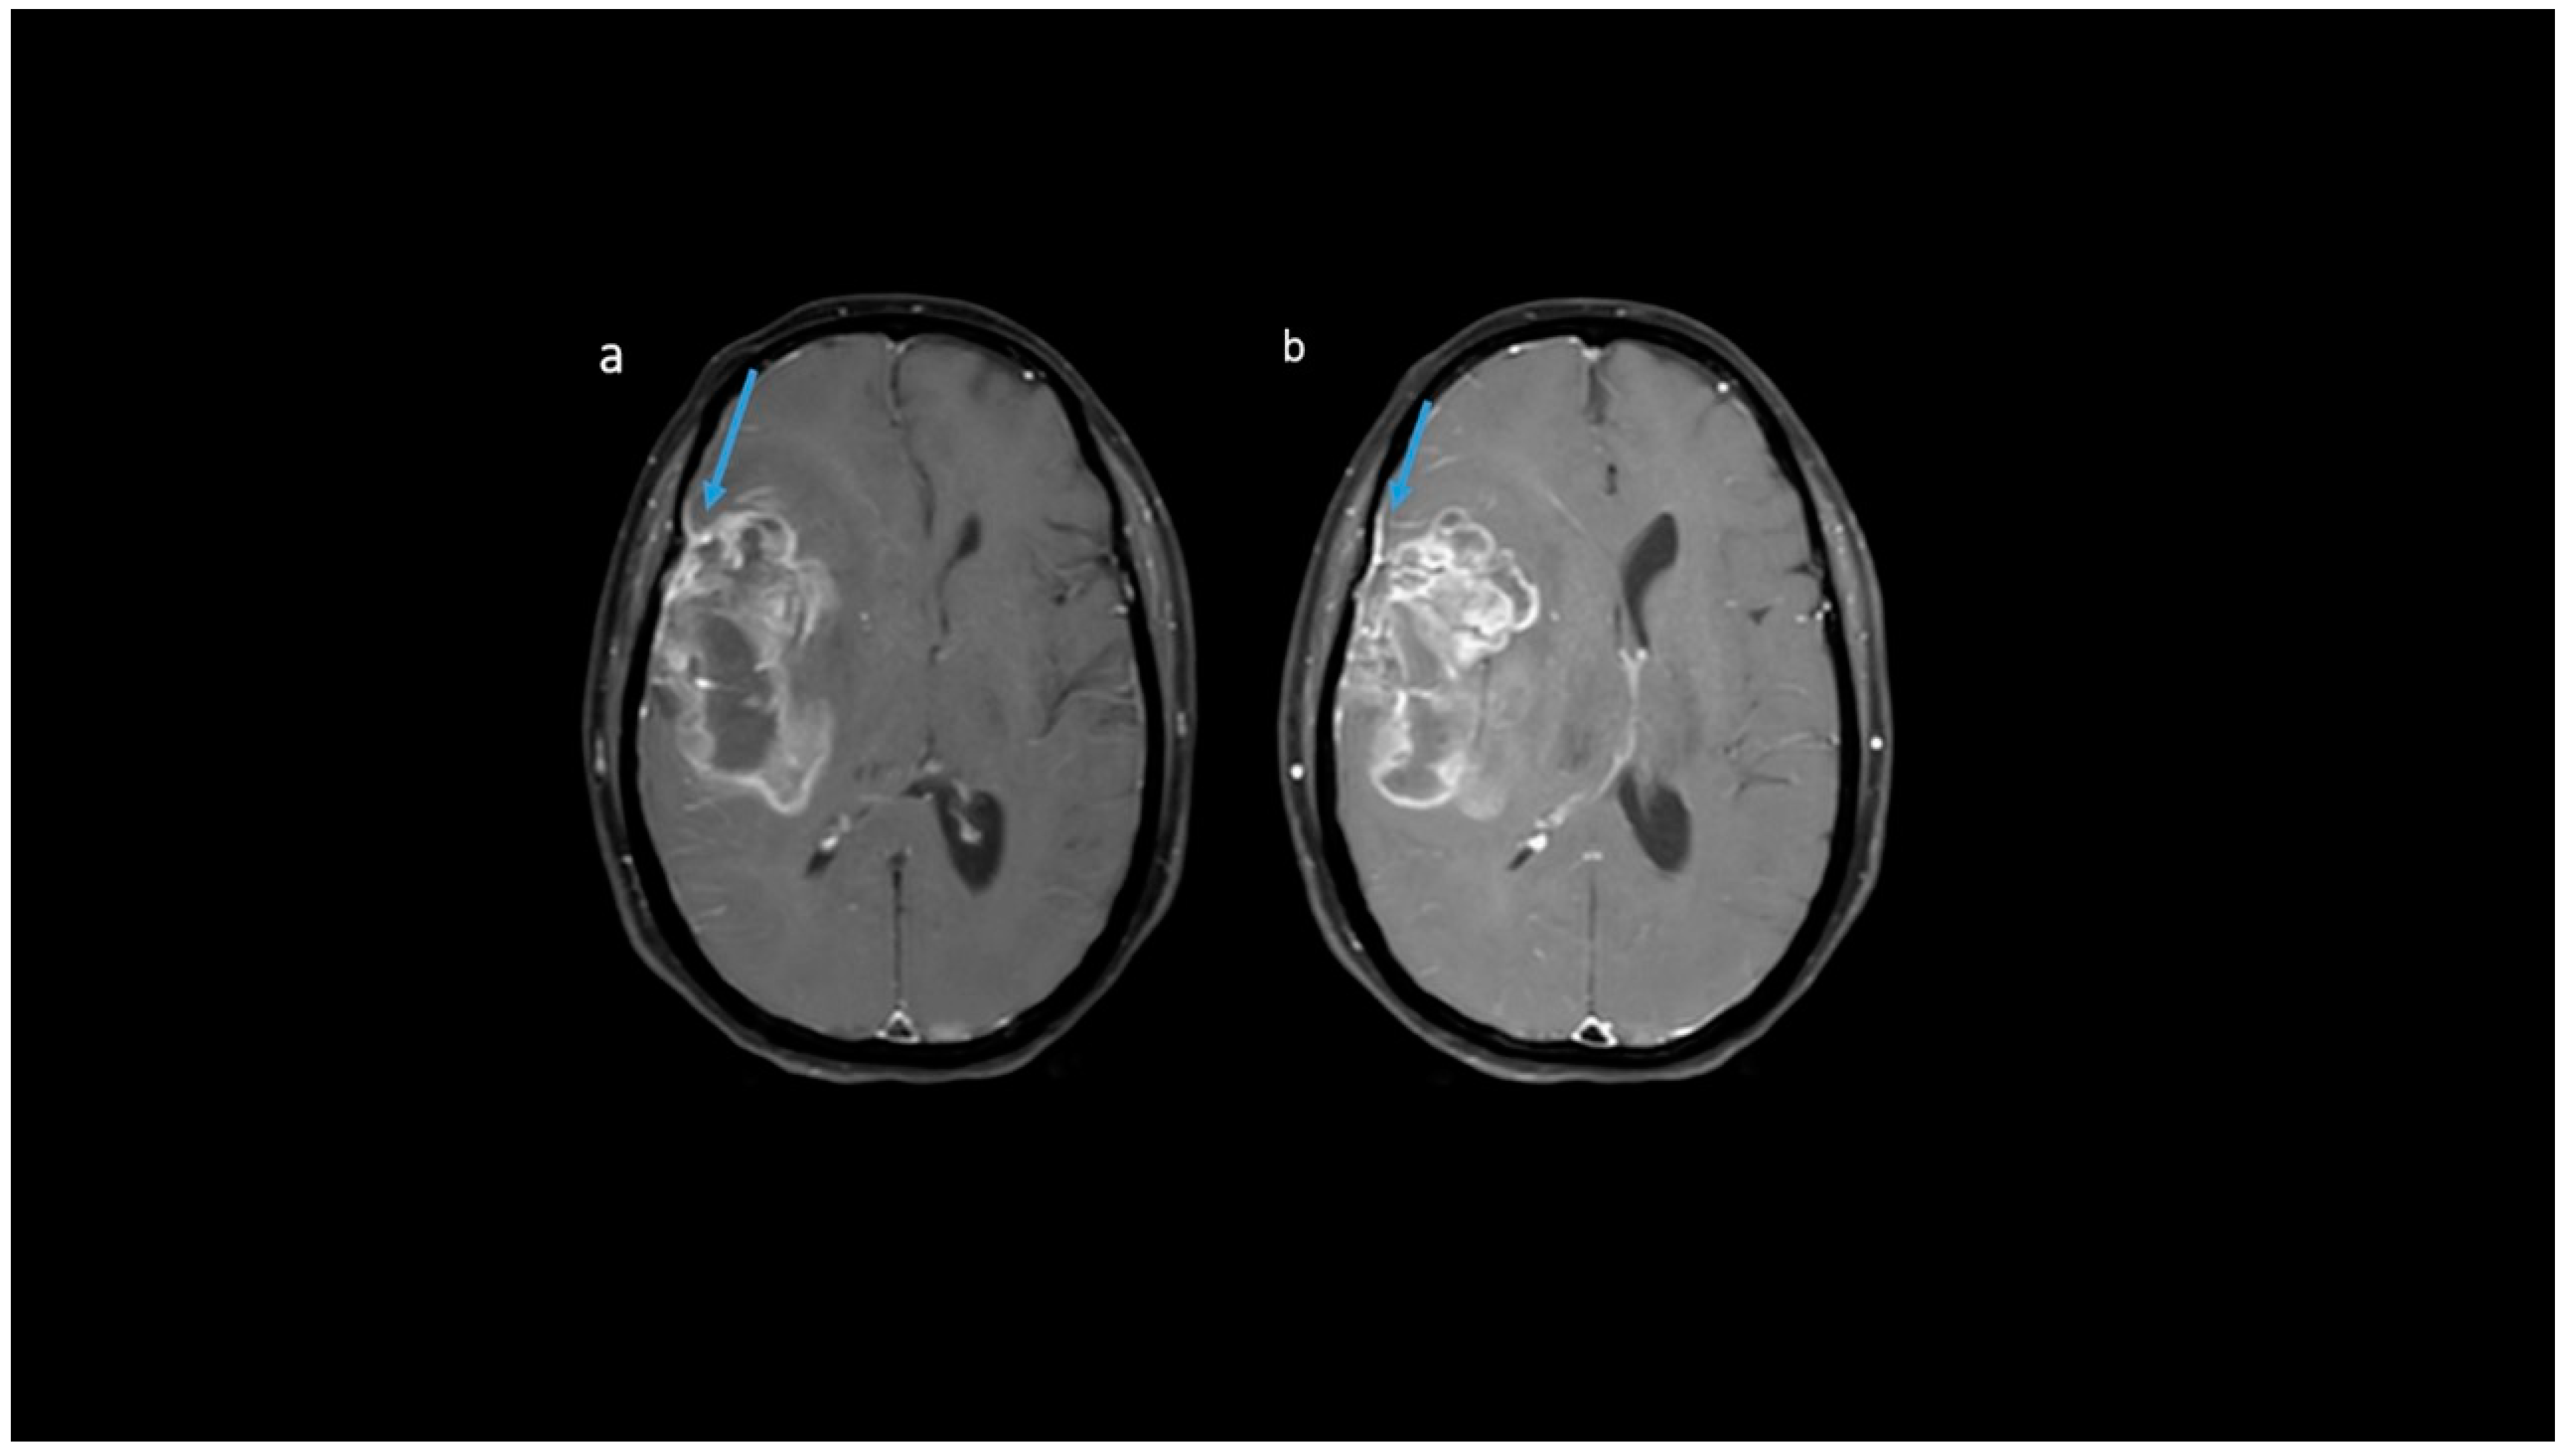

3.2. MRI Parameters of IDH-Wildtype vs. Mutant Phenotype Tumors